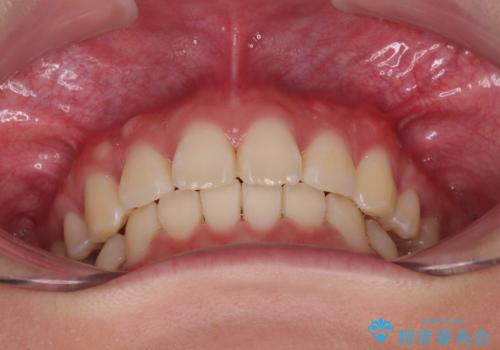

- 前歯部のデコボコと口元が出ているのが気になるとのことで来院された患者様です。

口元の突出感の解消と、このままデコボコを解消するとさらに出っ歯傾向になってしまうことを考慮し、上下左右の小臼歯を抜歯しクリアブラケットにて矯正していくこととしました。

舌突出癖を改善するトレーニングを一生懸命やっていただいたおかげで2年以内に治療を終えることができました。